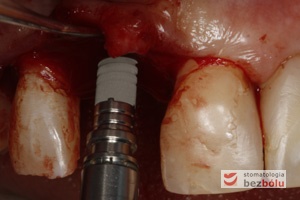

Filary protetyczne przygotowane do pobrania wycisku - transfery wyciskowe typu "bałwanek" przykręcone do implantów - zęby po redukcji dziąsła

Filary protetyczne przygotowane do pobrania wycisku – transfery wyciskowe typu „bałwanek” przykręcone do implantów – zęby po redukcji dziąsła

Transfery wyciskowe - widok z przodu - przenośniki typu "bałwanek" dedykowane pojedynczym implantom

Transfery wyciskowe – widok z przodu – przenośniki typu „bałwanek” dedykowane pojedynczym implantom